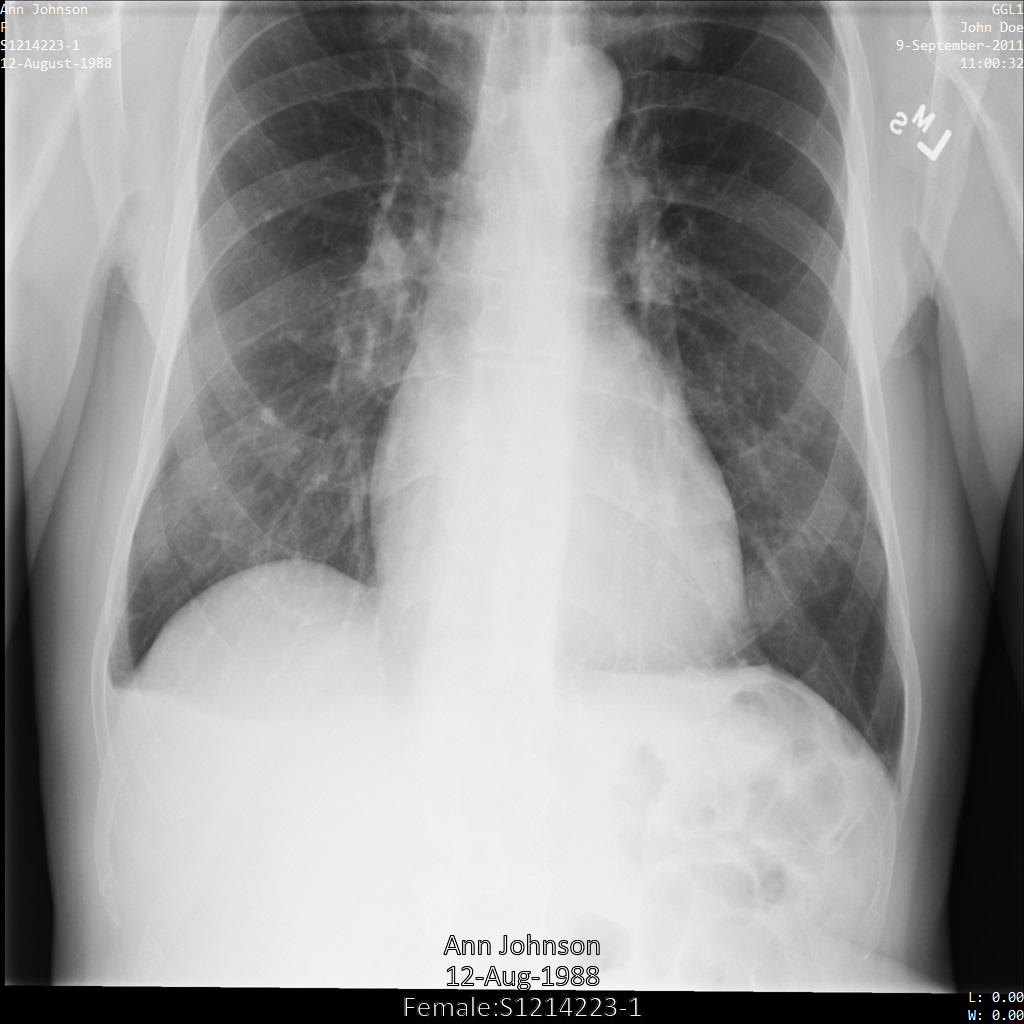

En cada una de las siguientes secciones, se proporcionan ejemplos de cómo desidentificar datos de DICOM mediante varios métodos. Se proporciona un resultado de la imagen desidentificada en cada muestra. En cada muestra, se usa la siguiente imagen original como su entrada:

Puedes comparar la imagen de salida de cada operación de desidentificación con esta imagen original para ver los efectos de la operación.